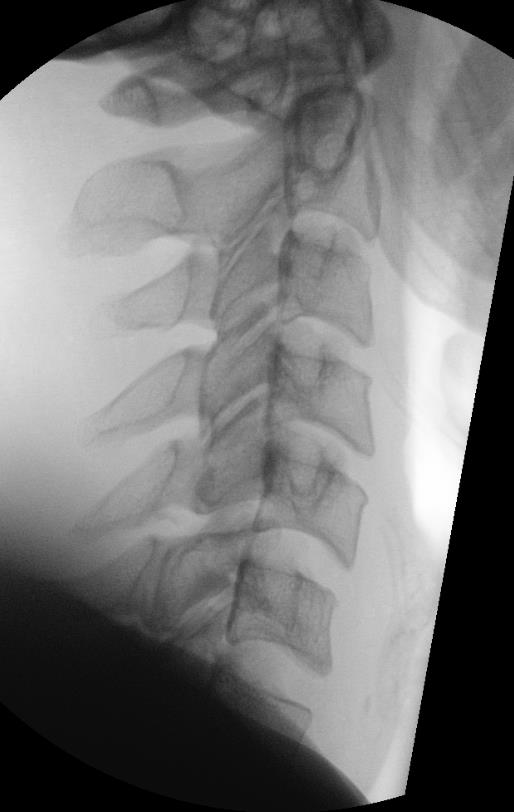

Bilateral Facet Joint Dislocation

>50% forward subluxation

Bilateral jumped facets on CT